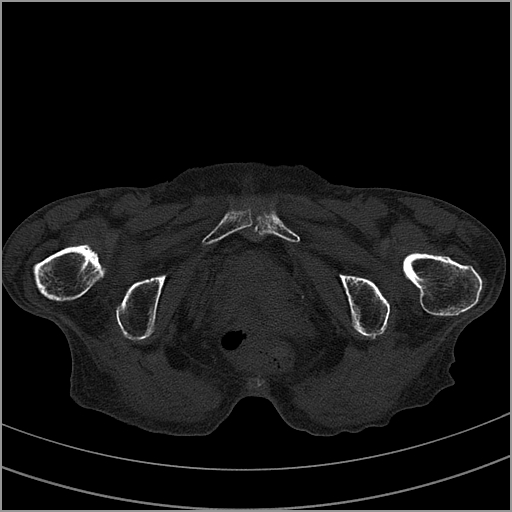

以下是引用老爱克斯新网客在2009-2-3 19:42:00的发言:[br]右侧髋臼及右侧股骨头可见明显骨质破坏,以溶骨性破坏为主,无明显硬化,髋关节间隙变窄,周围软组织明显肿胀,密度不均,脂肪间隙消失。[br] 诊断:右侧髋关节感染性病变,右侧髋关节结核的可能大。[br] 鉴别诊断:1.股骨头缺血坏死,单纯股骨头缺血坏死病例不会累积髋臼骨破坏。2。退行性关节炎,以骨质增生为主,伴有关节面硬化,骨质破坏呈多发小囊状破坏为主,其周围可见硬化环。3.股骨头缺血坏死晚期(第四期)骨质破坏可伴髋关节退行性变,可有骨质增生,但此时骨破坏以股骨头破坏为主,不应该伴有髋臼骨质破坏,因为股骨头的骨破坏是因血运中断,而没有髋臼的血运中断,又没有细菌的感染,怎么能造成髋臼的骨破坏呢。